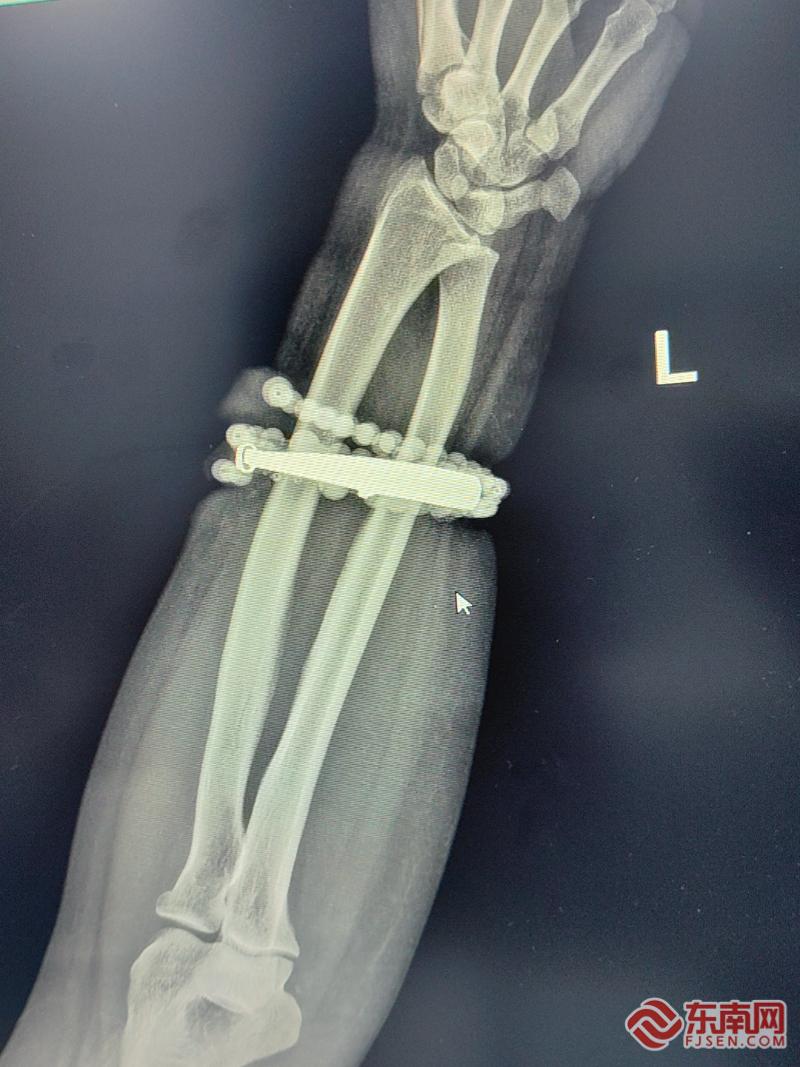

影像图。闽东医院供图